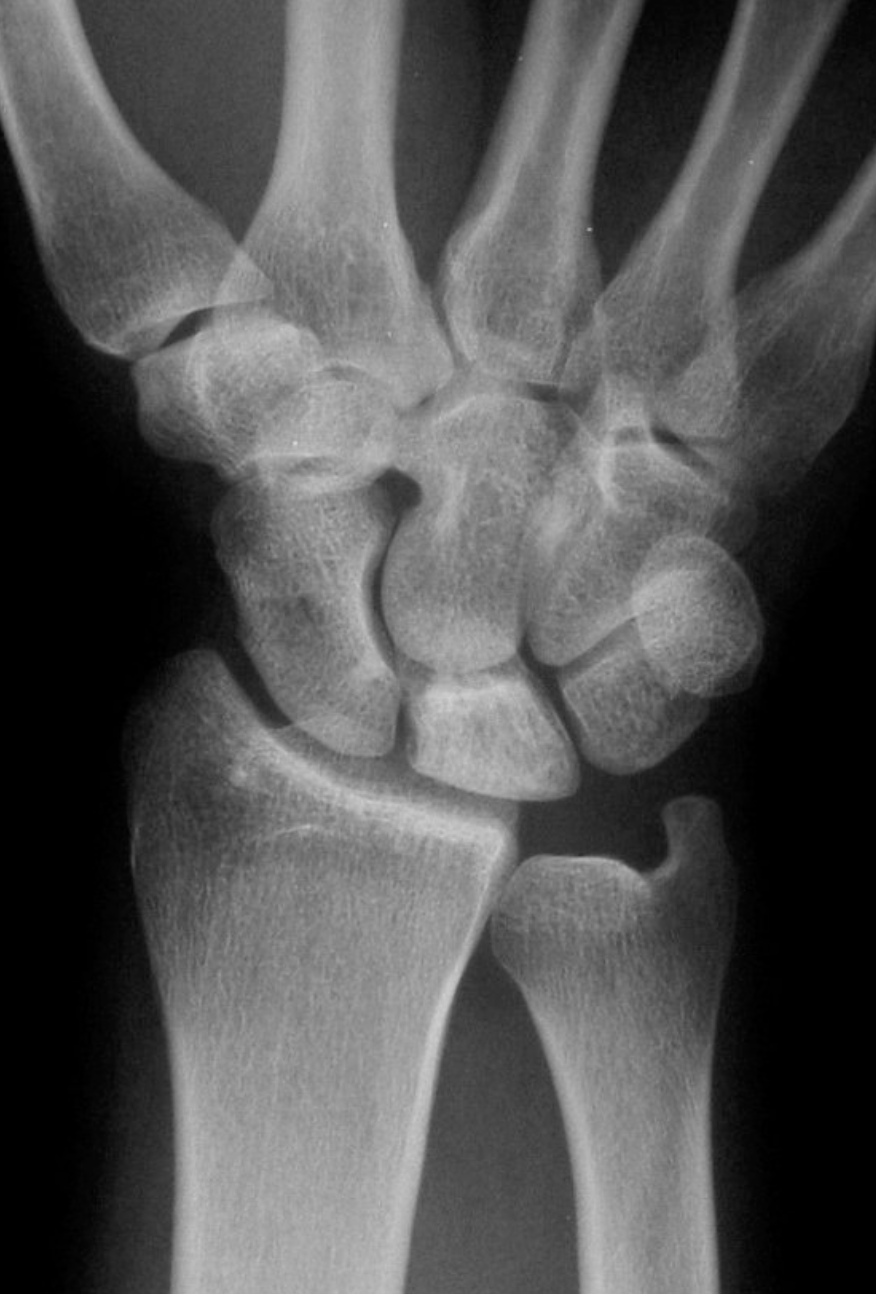

It is actually difficult to determine what will be the natural history of Kienbock’s disease in patients who first present. The condition is sometimes diagnosed very early on, before any xray changes are seen. In other patients the condition presents when the lunate bone fractures or breaks because of bone death.

Kienbock’s disease can be classified according to the changes seen on xrays and scans, and we try to classify the condition in all patients, so that we can give an idea of what is likely to happen. If, for example, a patient presents with stage 2 Kienbock’s, but 6 months later has progressed to stage 3, then we assume that the disease process is active. If no progression of the condition is seen on serial xrays, then we can say that the disease process is static.